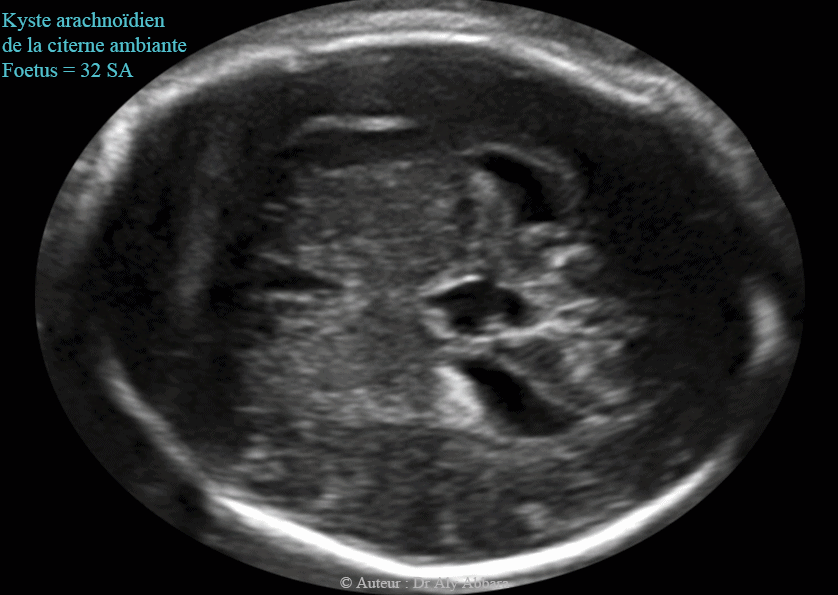

Images échographiques animées montrant la présence d'un probable kyste arachnoïdien cérébral (ou neuroépithélial) évoluant dans la citerne ambiante (en arrière du corps calleux) et mesurant 11 x 18 x 9 mm et associé à une ventriculomégalie bilatérale se caractérisant par l'élargissement des deux carrefours ventriculaires postérieurs qui mesurent 11 - 12 mm de largeur.

Le 3e et le 4e ventricules ne sont pas dilatés.

Il s'agit d'une anomalie isolée chez un foetus de 32 SA; aux échographies du 2e trimestre ce kyste n'était présent.